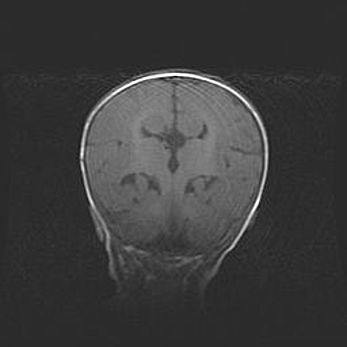

Открытая гидроцефалия.

Возраст: 9 месяцев 12 дней

Вес: 6800 г

Пол: мужской

Окружность головы: 41,5 см

Срок гестации: 28 недель

Гидроцефалия головного мозга у новорожденных имеет характерный признак: опережающий рост окружности головы приводит к визуально хорошо определяемой гидроцефальной форме сильно увеличенного в объёме черепа. Детские неврологи определяют следующие симптомы гидроцефалии у грудничков: выбухающий напряжённый родничок, частое запрокидывание головы, смещение глазных яблок к низу.